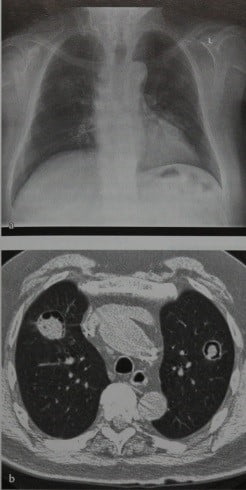

Визуализация и диагностика неинвазивного аспергиллеза с помощью КТ

Раздел: Необычные решения